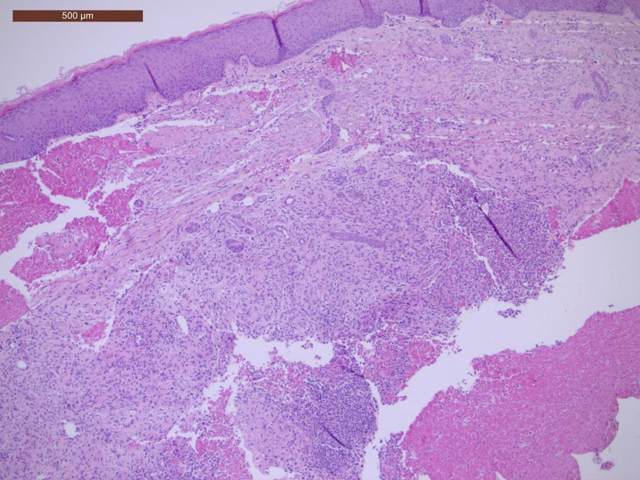

在医学上,克罗恩病被分为几种不同的临床类型,每一种都有其特定的症状和治疗方案。从最初的诊断开始,我就被分类为“炎症型”。这个类型的特点是肠道炎症反应频繁,伴随剧烈的腹痛和腹泻。每一次发作,都像是一场突如其来的风暴,让我措手不及。